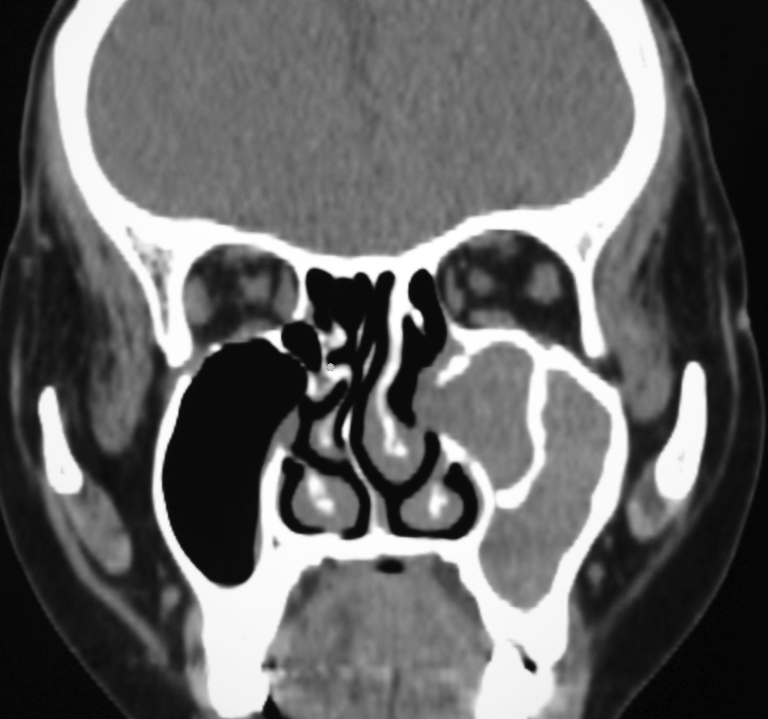

МРТ головного мозку: від пошуку причин мігрені до ранньої діагностики інсульту

Статті Автор: Ан-Сі-Тек Тетяна

Головний біль, запаморочення або раптова слабкість — симптоми, які ми часто списуємо на втому чи погоду. Проте наш мозок — це надскладний «командний центр», який потребує…

Вогнища гліозу та кісти мозку: чи варто панікувати після МСКТ?

Після проходження МСКТ (мультиспіральної комп’ютерної томографії) головного мозку пацієнти нерідко отримують висновки з формулюваннями «вогнища гліозу», «лікворна кіста» або «розширення арахноїдальних просторів». Такі терміни можуть звучати…

МРТ при розсіяному склерозі: читаємо протокол за критеріями Макдональда

Статті Автор: Alla Kovshova

Розсіяний склероз (РС) — це захворювання, яке часто називають «хворобою з тисячею облич» через різноманітність симптомів. Проте в його діагностиці існує чіткий світовий стандарт — критерії…